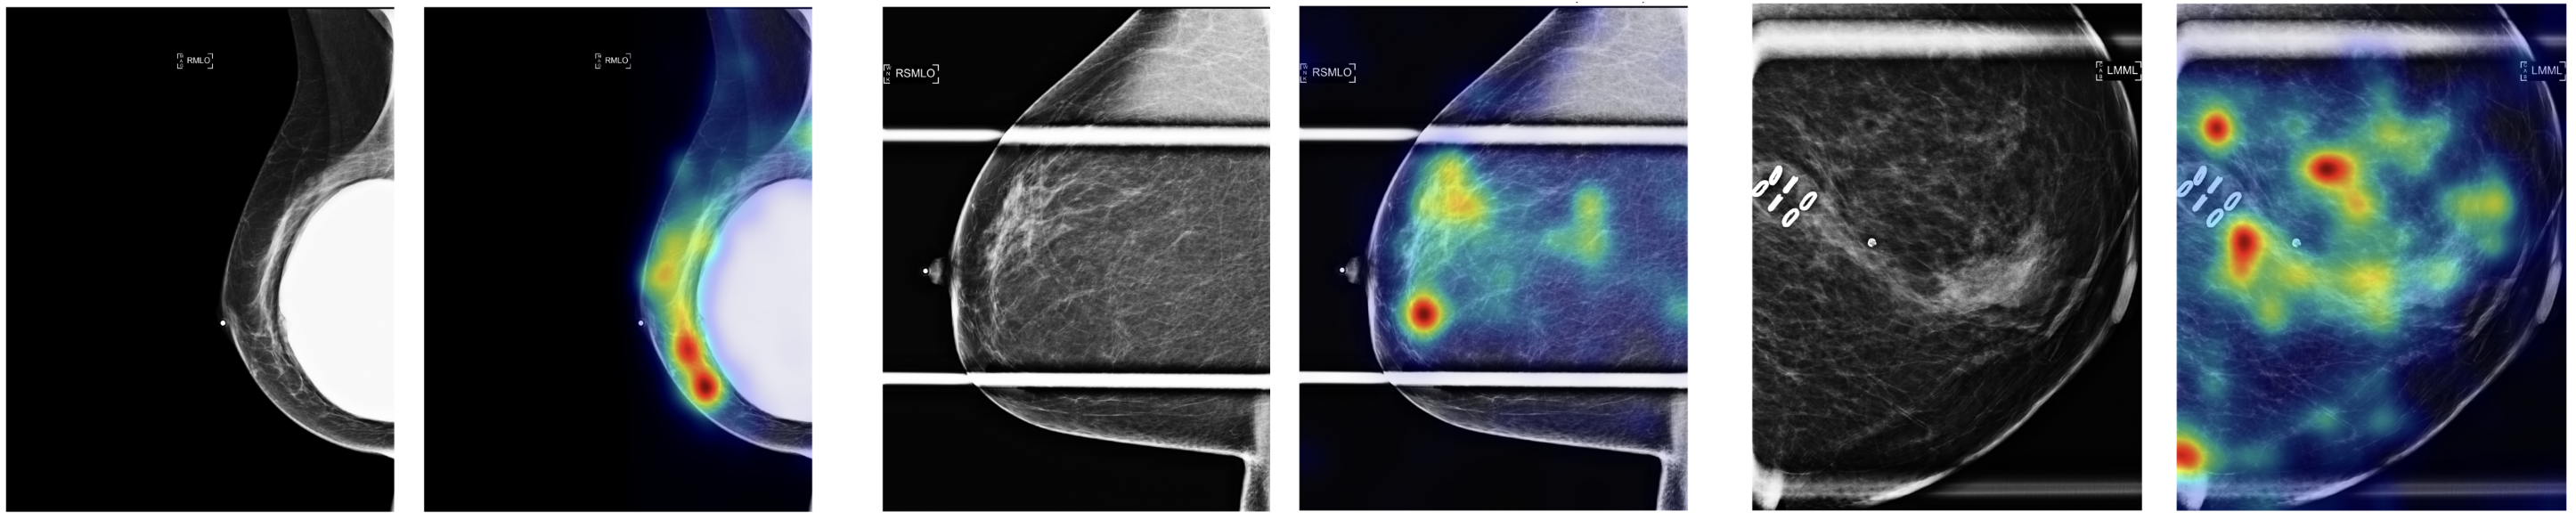

We use GradCAM [gradcam] to generate saliency maps (Figure 1) to show the attention patterns of the model and to identify the features that differentiate the four breast density grades. In fatty or almost entirely fatty breasts (Fig. 1A), the model’s attention is diffusely distributed across the entire breast area. In contrast, for scattered (Fig. 1B), heterogeneously dense (Fig. 1C), and extremely dense breasts (Fig. 1D), the model’s attention is concentrated in regions with higher amounts of fibroglandular tissue. Zero-shot classifications on external dataset shows that the model maintains consistent attention even on unseen data (Figure 2).

Refer to caption

Figure 1: Grad-CAM visualizations across BI-RADS categories A–D (left) and confusion matrix on the validation set (right), using data from a single site (s2D only). Note: Warmer colors indicate higher model attention.

Model robustness was visually evaluated on external datasets with significant variations in imaging protocols. Figure 3 demonstrates the model’s ability to maintain accurate predictions while focusing attention on anatomically relevant tissues, even in the presence of compression paddles, clips, and implants; The model focus on density patterns and fundamental characteristics, rather than relying on dataset-specific features.

Figure 3: GradCAM visualizations demonstrating model robustness to imaging variations (paddles, annotations, implants) while maintaining focus on breast tissue density patterns.